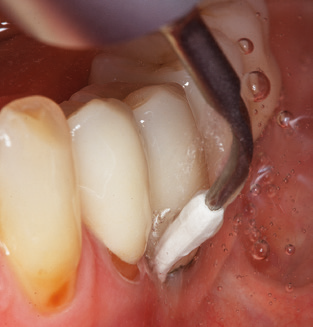

Nach der maschinellen Reinigung der Zahn und Implantatoberflächen erfolgt eine manuelle Instrumentierung der natürlichen Zahnoberflächen mit konventionellen Handinstrumenten. Bei der manuellen Reinigung ist insbesondere auf einen korrekten Anstellwinkel, eine ausreichende Schärfe, eine gute Abstützung und auf eine von apikal nach koronal gerichtete Arbeitsweise der Kürette zu achten. Zur Nachinstrumentierung der Implantatkonstruktionen sollten entweder Titan oder Carbonküretten verwendet werden (Abb. 8). Ergänzend zum Einsatz von Ultraschallgeräten können in der Erhaltungstherapie auch Pulverstrahlgeräte genutzt werden. Dabei ist jedoch zu berücksichtigen, dass diese Verfahren nicht zum Entfernen harter Beläge geeignet sind und daher die Verwendung von Hand oder Ultraschallinstrumenten nicht komplett ersetzen können. Abschließend erfolgt in jedem Fall eine mechanische Politur der zugänglichen Zahn und Implantatoberflächen mit Polierkelchen und Polierpasten (Abb. 9).